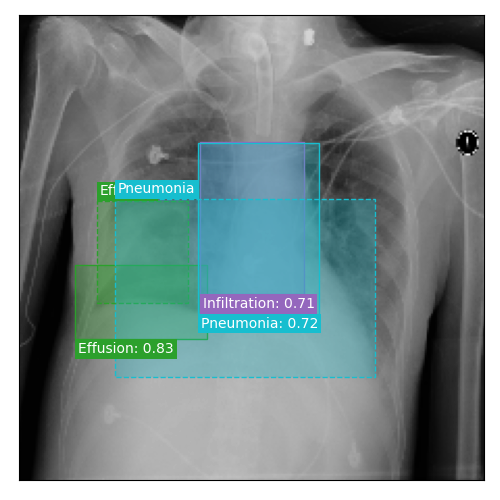

Qualitative Results

As shown in Fig. 4 Loc-ADPD detects cardiomegaly almost perfectly, as it is always exactly localized at one anatomical region. Other pathologies are detected but often with too large or too small boxes as they only cover parts of anatomical regions or stretch over several of them, which cannot be completely corrected using WBF. Detection also works well for predicting several overlapping pathologies. For qualitative comparisons between Loc-ADPD and MIL-ADPD, we refer to Appendix 0.B.

Appendix 0.B Qualitative Results and Failure Cases

| Loc-ADPD | MIL-ADPD | Loc-ADPD | MIL-ADPD |

![]() |

| (a) | (b) | ||